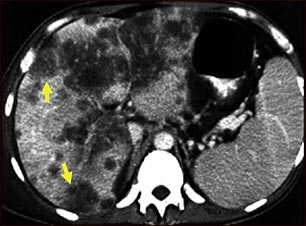

Tomografía computarizada de cáncer hepatocelular

Una tomografía computarizada de la parte superior del abdomen que muestra un carcinoma diseminado del hígado (carcinoma hepatocelular). El hígado es el órgano grande al lado izquierdo de la imagen y presenta una apariencia de haber sido devorado por polillas.